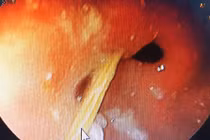

Trong quá trình phẫu thuật, các bác sĩ phát hiện ổ áp xe lớn, đường kính hơn 10 cm, nằm ở thùy gan trái và dính vào bờ cong nhỏ của dạ dày. Bên trong, có một chiếc tăm tre dài khoảng 5 cm đã cắm sâu vào nhu mô gan.

May mắn cho bệnh nhân là ổ áp xe còn khu trú tại gan chứ chưa vỡ có thể gây viêm phúc mạc (có thể nguy hiểm đến tính mạng bệnh nhân) điều này giúp quá trình phẫu thuật diễn ra thuận lợi hơn. Các bác sĩ đã cắt bỏ thùy gan trái kèm ổ áp xe và lấy dị vật. Sau phẫu thuật, bệnh nhân tỉnh táo, ổn định hồi phục nhanh chóng.